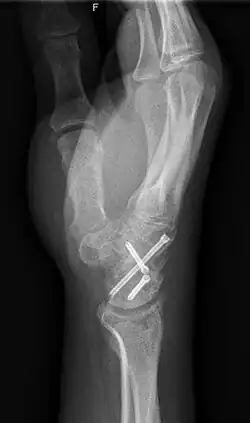

X-ray of a wrist that has undergone carpal arthrodesis (fusion of the wrist joint). In this case, this means that screws have been inserted through multiple wrist bones so they are now immobilized. Over time, these bones will fuse together, preventing them from rubbing against each other and causing pain.

Arthrodesis is the surgical immobilization of bones within a joint to promote fusion of the joint.[20] Arthrodesis is performed most commonly on joints of the feet, hands, and spine.[21][22][23] Arthrodesis can relieve pain from arthritis and fractures.[24] This is accomplished through the use of orthobiologics such as allografts and autografts.[25] Allografts are done by creating bone grafts from a donor bone bank, whereas autografts are bone grafts from other bones in a patient's body.[25] Patient-reported outcomes following this procedure are typically positive in terms of long-term pain relief; however, the procedure also results in decreased range of motion.[26]